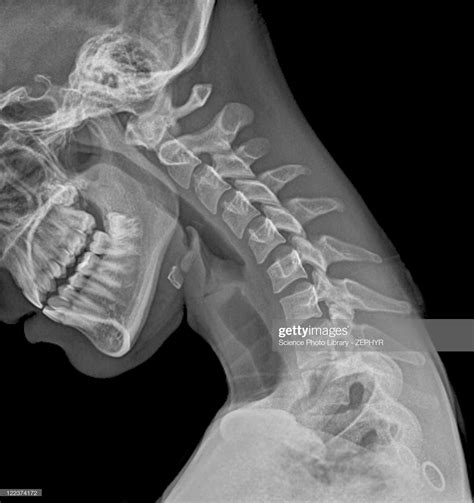

A Normal Neck X Ray is a radiographic imaging technique used to visualize the bones, joints, and soft tissues of the neck. It is a non-invasive procedure that helps in diagnosing a wide range of conditions, including fractures, dislocations, arthritis, and infections. The term “normal” in this context refers to the expected appearance of the neck structures in the absence of any pathological conditions.

Interpreting a Normal Neck X Ray involves examining the images for any abnormalities. Key structures to assess include:

• Vertebrae: The seven cervical vertebrae (C1-C7) should be clearly visible and aligned.

• Intervertebral Discs: The spaces between the vertebrae should be uniform and without narrowing.

• Joints: The facet joints should be well-defined and without signs of degeneration or inflammation.

• Soft Tissues: The soft tissues, including muscles and ligaments, should appear normal without any swelling or masses.

• normal neck x ray images

• normal neck x ray female

• normal neck x ray pediatric